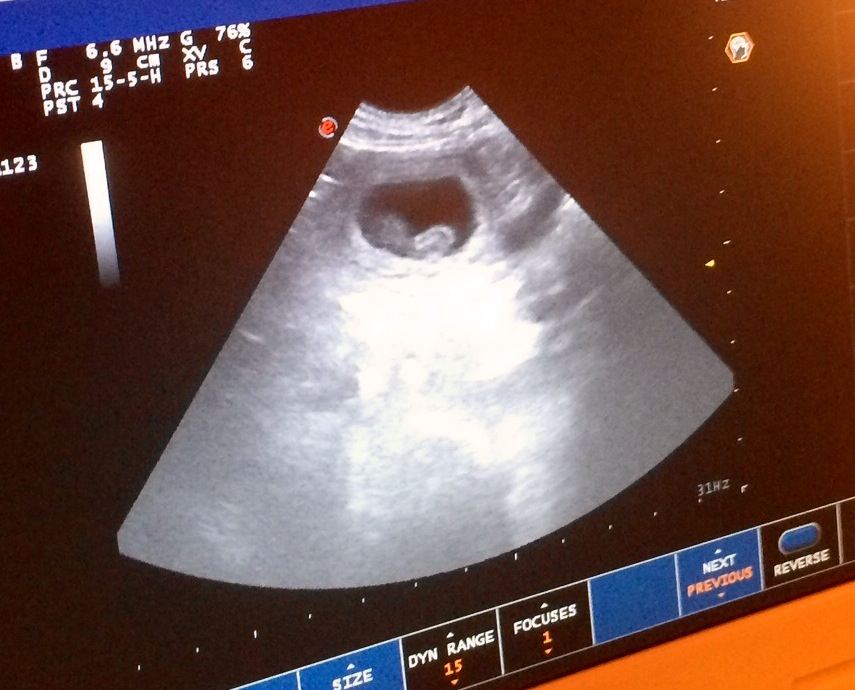

Vi har vært på ultralyd…

og gleden er stor, for det viser seg at Bitten er drektig! Undersøkelsen viste at hun venter et middels stort kull, antakelig 4-6 valper 🙂

Fostrene er nå omtrent 1,7 cm lange, og man kan se fosterposer og små hjerteslag 🙂 Her kommer noen bilder fra ultralydundersøkelsen. Fotograf er Tommy Bratteng.